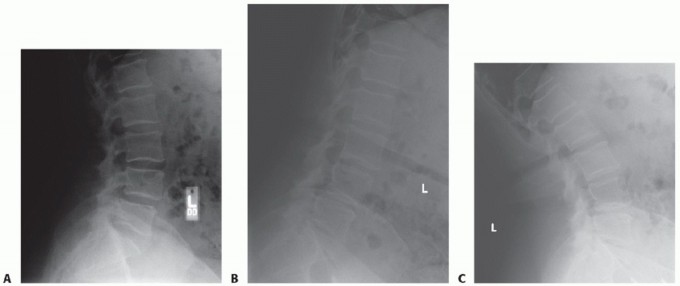

Slipped disc: Non-surgical treatment options Most people with a slipped disc in the lumbar region of their sp…